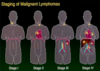

Where are most neoplastic cells in leukemia?

Where are most neoplastic cells in lymphoma?

Where are most neoplastic cells in myeloma?

Where are most neoplastic cells in Hodgkin’s disease?